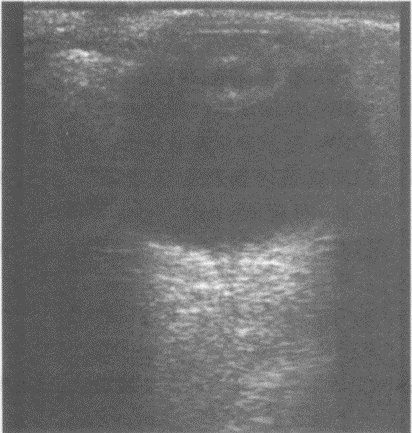

如图所示,双肾结构清晰,左肾体积小,该病例最可能诊断是()。

A:肾发育不良

B:肾萎缩

C:慢性肾炎

D:肾结核

E:慢性肾衰